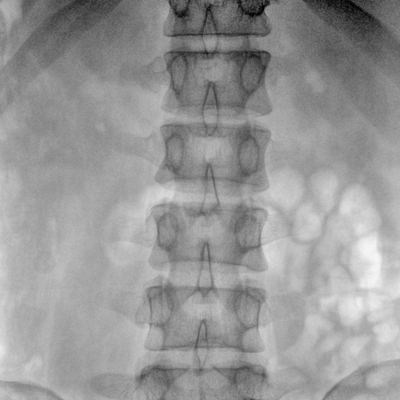

大尺寸動(dòng)態(tài)平板探測器,高DQE、低噪聲、圖像清晰。采用多分辨率圖像增強處理技術(shù),不同部位不同圖像處理算法,滿(mǎn)足客戶(hù)多樣化的需求。

采用智能變頻脈沖透視技術(shù),優(yōu)化圖像質(zhì)量的同時(shí)降低輻射劑量,呵護醫患健康